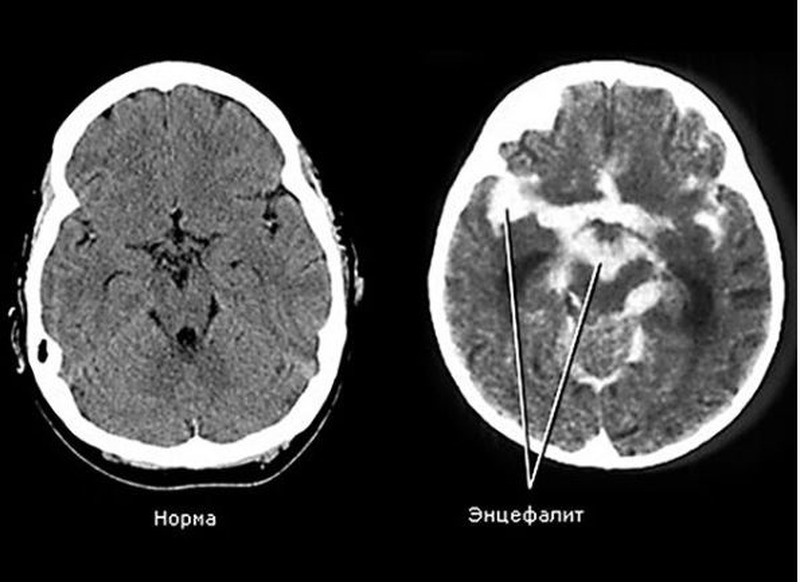

МРТ головного мозга:

• При герпетическом энцефалите: гиперинтенсивность в медиальных отделах височных долей

• При аутоиммунном энцефалите: изменения в лимбической системе

• При клещевом энцефалите: поражение ствола мозга и таламусов